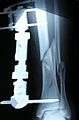

X-Ray of fracture and initial external fixator applied within 24 hours of patient's admission to hospital

X-Ray of the fracture site immediately following the application of the Ilizarov method